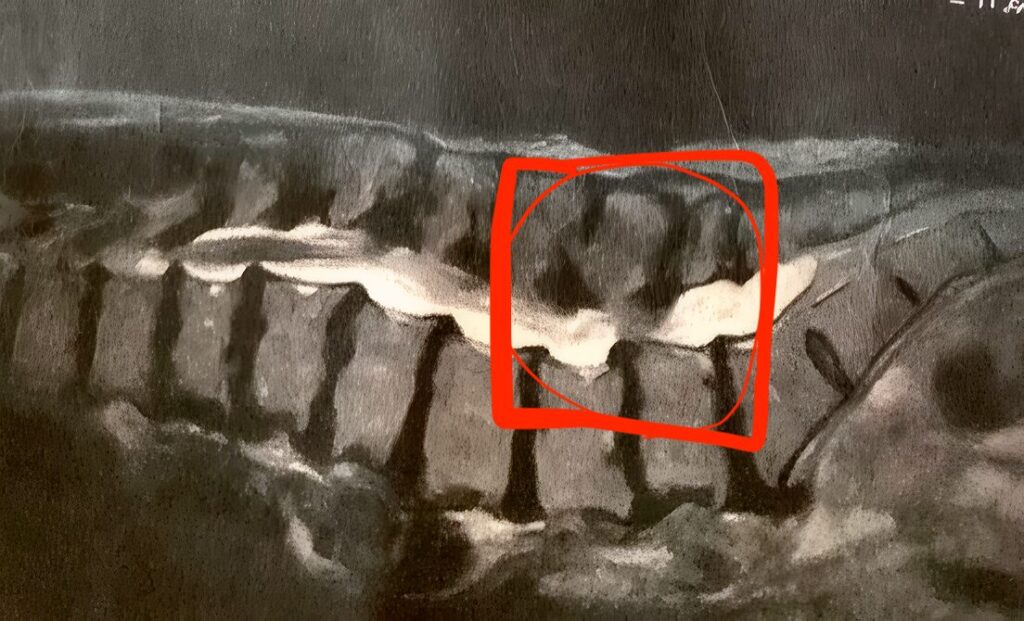

実際のMRI画像です。↑

腰の赤く囲った部分が狭窄症の症状です。